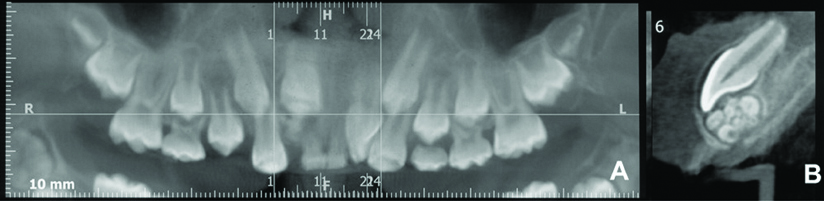

After performing periapical and panoramic radiographs, a cone beam volumetric computed tomography was suggested [Table/Fig-2a]. A circumscribed lesion formed by small hyperdense masses like denticles, surrounded by a hypodense halo [Table/Fig-2b] was found, suggesting the provisional diagnosis of compound odontoma.

a) Panoramic and b) approximated view of the lesion in the cone beam computed tomography.